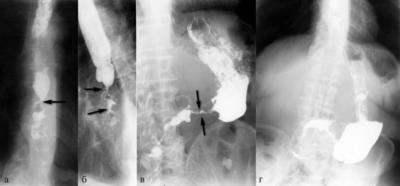

A szövettani vizsgálat a nyelőcső eltávolítása után végzett 3 esetben, a széleit a nyelőcső-mediasztinális sipoly után fibroezofagoskopii - 1 fő esetében. nyelőcső változások a stent minden esetben azonos, és képviseli a gyulladás különböző súlyosságú. A nyálkahártya talált szabálytalan hangsúlyos acanthosis, bazális réteg hiperaktivitás, dyskeratosis fejlesztésével a granulációs szövet a proximális és disztális végei a stent. A nyálkahártya alatti réteg feltárt infiltrációja limfociták, plazma sejtek és a makrofágok (ábra. 7).